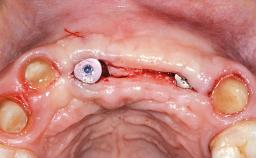

A 45-year-old woman was referred for management of an infection associated with two implant-supported crowns replacing the maxillary central incisors. Two tissue-level implants had been placed and restored with cemented single metal-ceramic crowns in those sites 4 years previously. The patient presented with a draining sinus (i.e. a pathological duct from an abscess cavity to a surface) 3 mm from the midfacial peri-implant mucosal margin of the maxillary right implant crown. She was in good general health, did not smoke, showed a good oral hygiene status, and had no history of periodontal disease. The implants were well positioned. While the patient was very satisfied with the appearance of her crowns, she had noted that the peri-implant soft tissue had receded since their insertion and was concerned about the possibility of further recession.